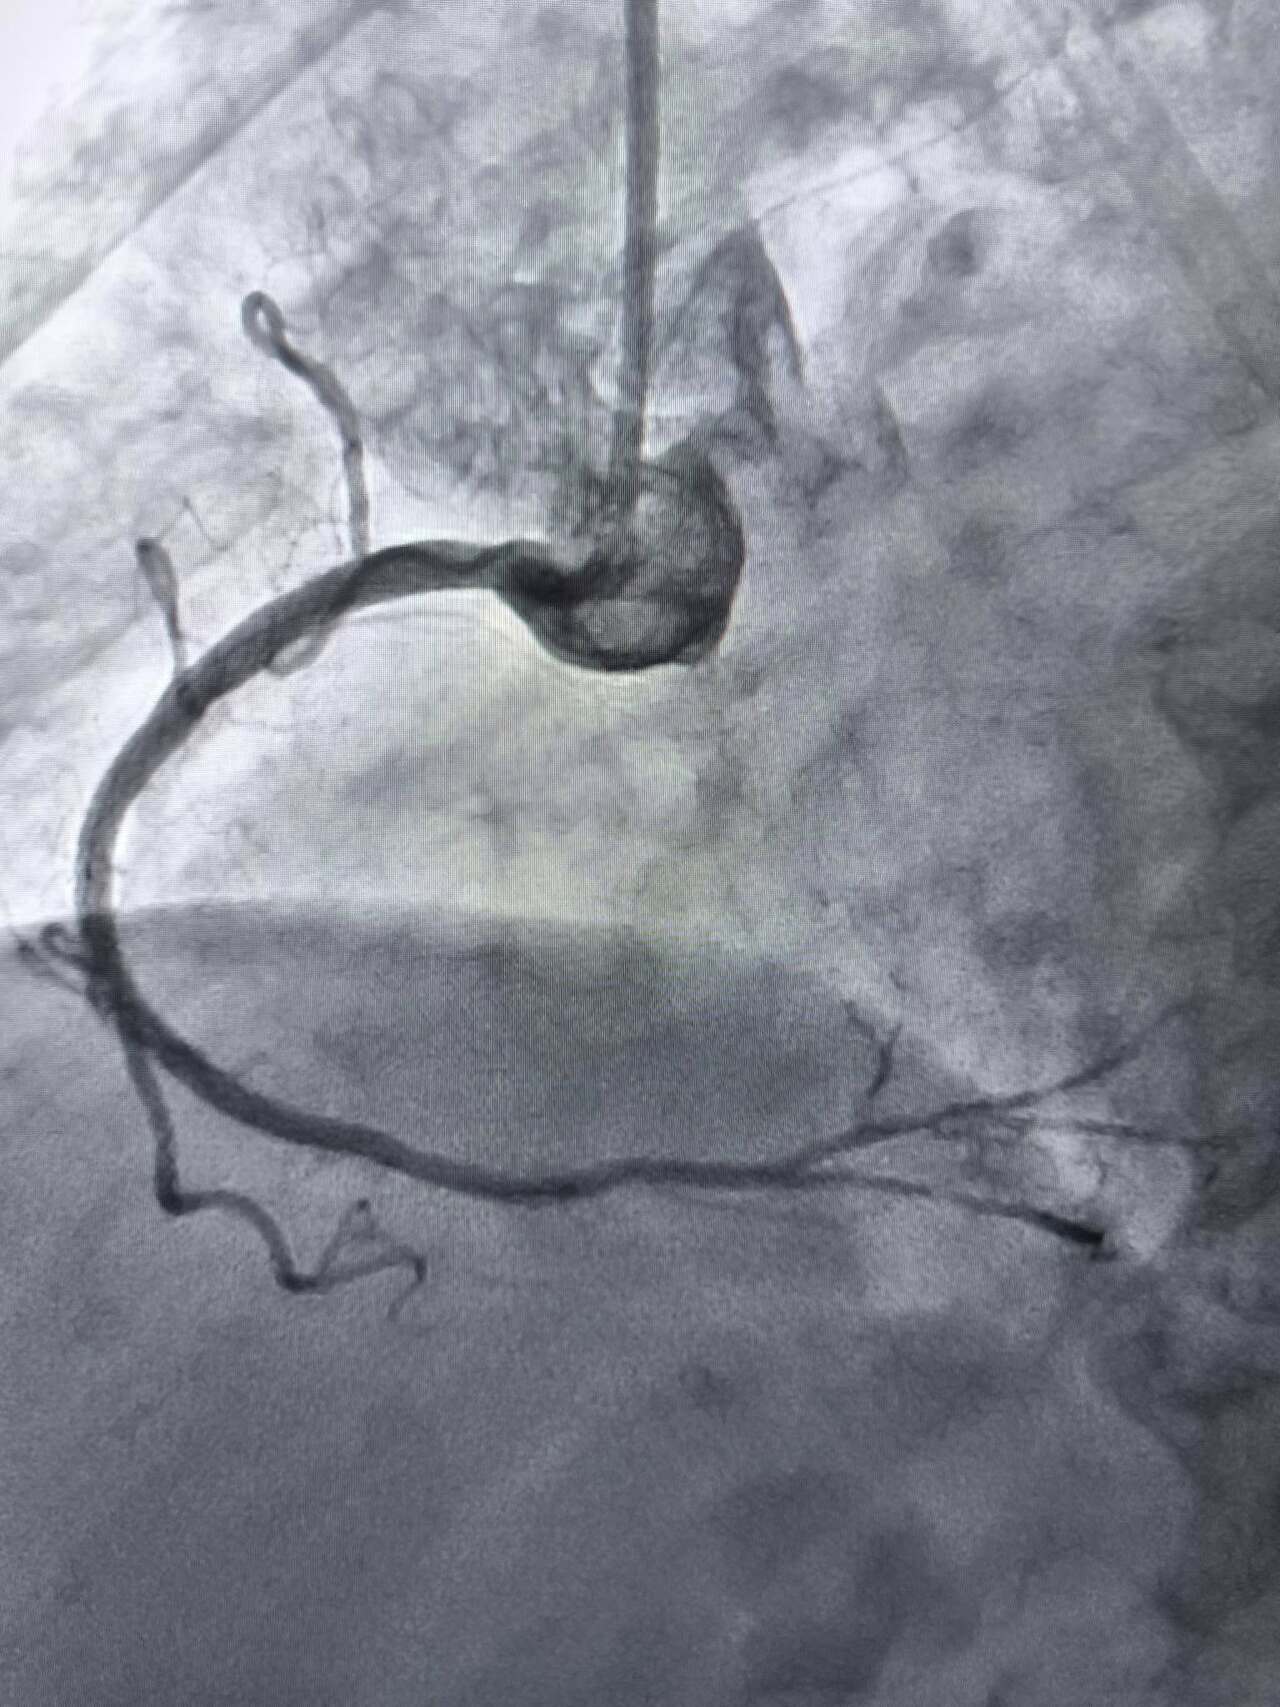

Високотехнологічну процедуру – ротаційну атеректомію вперше на Тернопільщині провели в обласній клінічній лікарні. Про це повідомили у пресслужбі лікарні.

Йдеться про складне втручання, яке застосовується у випадках вираженого кальцинозу коронарних артерій, коли стандартні методи не дають результату.

За словами завідувача відділення інтервенційної радіології, кардіології та реперфузійної терапії Богдана Маслія, у пацієнтки діагностували значне звуження правої коронарної артерії. Розширити її традиційним способом – шляхом роздування балона, не вдалося, навіть із використанням балона високого тиску до 25 атмосфер (це приблизно у десять разів більше, ніж тиск в автомобільному колесі).

У таких ситуаціях на допомогу приходить ротаблятор – спеціальний пристрій із буром, покритим діамантовим напиленням. Він дозволяє «модифікувати» кальциновану атеросклеротичну бляшку, фактично шліфуючи її та відновлюючи можливість для подальшого стентування судини. Саме таким методом лікарям вдалося ліквідувати перешкоду в артерії та успішно імплантувати стенти.

Це втручання стало важливим кроком для нашої лікарні та всієї області. Ротаційна атеректомія застосовується у найскладніших випадках кальцинованих уражень коронарних артерій, коли стандартна ангіопластика неефективна. Виконання такої процедури означає, що пацієнти Тернопільщини можуть отримати сучасну високоспеціалізовану допомогу без необхідності їхати в інші регіони, – наголосив Богдан Маслій.

Фото Тернопільської обласної клінічної лікарні